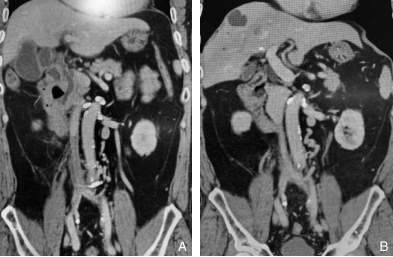

图1 重复球囊扩张治疗腔髂静脉闭塞 A:球囊扩张治疗前IVC血栓闭塞;B:3次球囊扩张治疗后IVC通畅Fig.1 Repeated balloon dilatation for the treatment of iliocaval venous occlusion A: Inferior vena cava thrombosis with occlusion before balloon dilatation; B: Restored patency of the inferior vena cava after three sessions of balloon dilatation